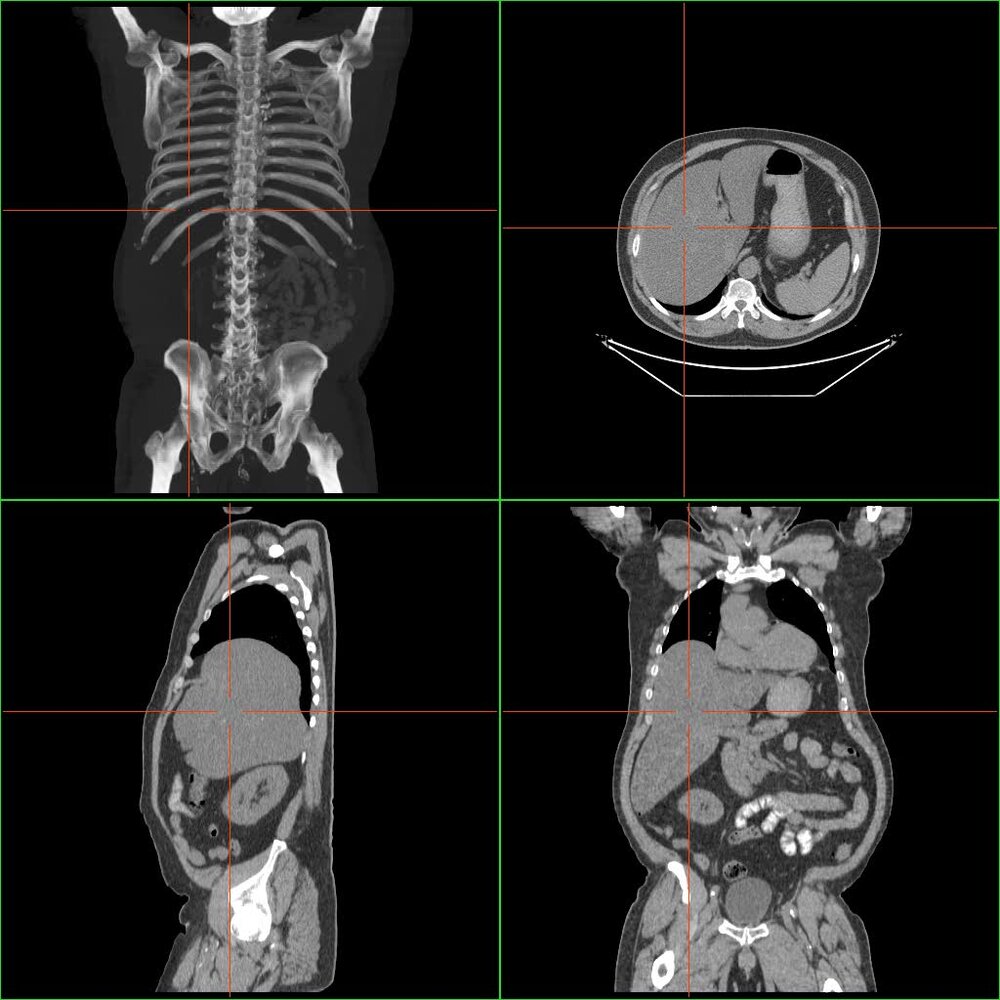

Imaging [1]

- CT head: Obtain initially to rule out alternative causes of altered mental status.

-

Abdominal ultrasound with Doppler: to assess liver damage [16]

Ultrasound findings

- Early: may include heterogeneous hypoechogenicity (sign of necrosis) and/or ascites

- Late: in patients who have been sick for at least seven days, may show a nodular surface, which can be mistaken for cirrhosis

- Doppler findings depend on the underlying cause, e.g., portal vein thrombosis, hepatic ischemia.

- Chest x-ray: to rule out cardiopulmonary complications

- ECG: to identify dysrhythmias